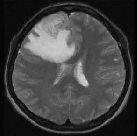

胶质瘤 ,是一种起源于大脑正常胶质细胞的肿瘤。那么胶质细胞又是什么呢?如果把神经元比作各类植物的话,胶质细胞就是孕育植物的土壤,即,广泛分...